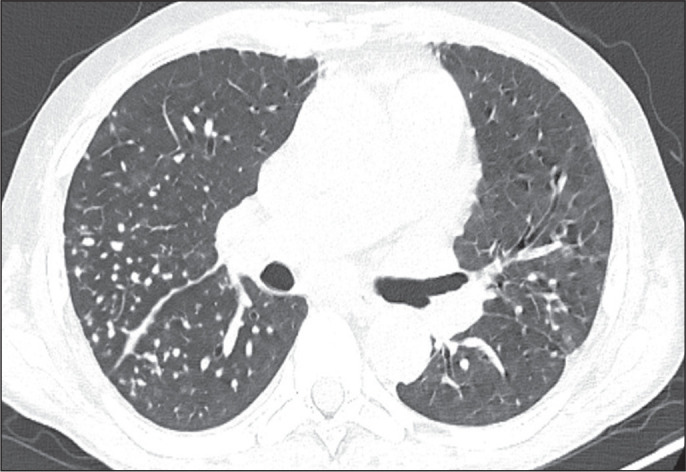

目的:评估2019冠状病毒(COVID-19)感染者典型CT扫描频率,并比较接种疫苗和未接种疫苗的人群。材料与方法:对2021年8月至2022年2月期间临床疑似COVID-19患者的病历进行回顾性研究。疫苗接种状态分为未接种/未接种(0或1剂)或已接种(2剂或更多剂)。在第一次胸部CT上所见的模式被定义为典型、非典型、不确定或正常,后三种模式被合并为非典型组。结果:二元logistic回归分析显示,完全接种疫苗的个体呈现典型CT模式的可能性低于未接种或不完全接种疫苗的个体(调整后OR = 0.19, 95% CI: 0.06-0.60)。结论:这一信息很重要,因为它表明,目前被认为是COVID-19典型的CT模式的频率低于疫苗可用之前的频率。因此,不再期望典型的CT表现。

Objective: To evaluate the frequency of the typical computed tomography (CT) pattern in individuals with coronavirus 2019 (COVID-19), comparing those who were vaccinated with those who were unvaccinated.

Materials and methods: This was a retrospective study of the medical records of patients with clinical suspicion of COVID-19 between August 2021 and February 2022. The vaccination status was classified as absent/incomplete (0 or 1 dose) or complete (2 or more doses). The pattern seen on the first chest CT was defined as typical, atypical, indeterminate, or normal, the last three patterns being combined to form what was designated the non-typical group.

Results: Binary logistic regression analysis showed that individuals with a complete vaccination status were less likely to present with the typical CT pattern than were those with an absent/incomplete vaccination status (adjusted OR = 0.19, 95% CI: 0.06-0.60).

Conclusion: This information is important because it demonstrates that the frequency of the CT pattern considered typical of COVID-19 is currently lower than it was before the vaccines became available. Therefore, the typical CT pattern is no longer expected.